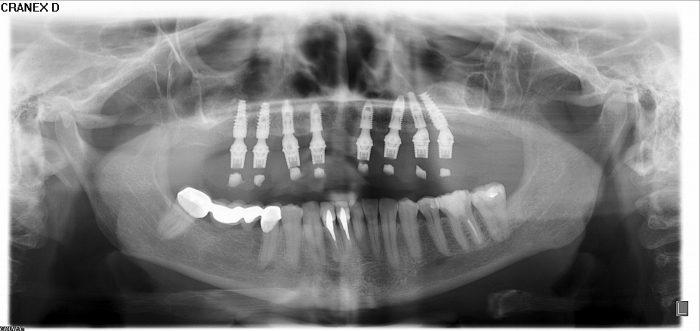

Raio-x Inicial

Raio - x Panorâmico Enxerto ósseo de crista iliáca